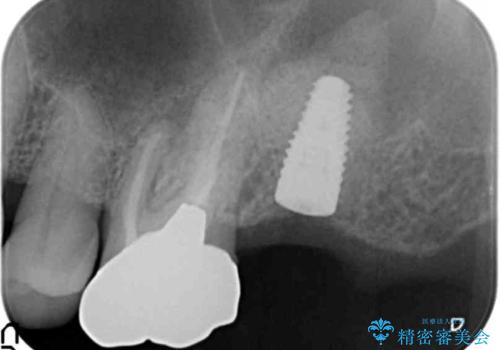

初診時から治療終了時までのレントゲンをお見せして説明差し上げたところ、「お~!骨ができている!」と喜んで下さいました。

ソケットリフトにより上顎洞底を挙上し骨造成することにより、骨の厚みが薄い部分でもインプラントが可能になります。

インプラントの種類:ストローマン BLT

クラウンの種類:メタルボンドクラウン エコノミー